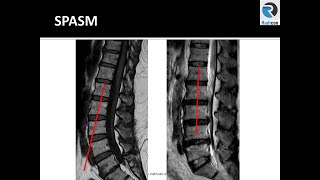

How to Read an MRI of the Lumbar Spine: A Beginner's Approach

MRI Anatomy of Lumbar Spine: Radiology Tutorial & Exam Prep